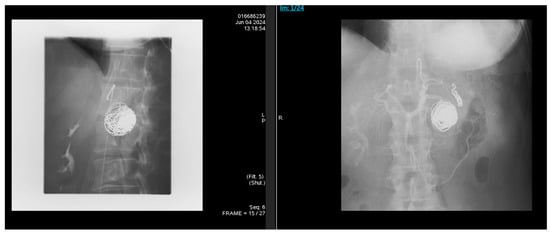

The patient had immediate visceral angiography with successful coil embolization of the splenic artery pseudoaneurysm. Covered stent placement was considered but not pursued due to anatomical constraints, including vessel tortuosity and caliber. Following the procedure, angiography confirmed total occlusion (Figure 3). Coil embolization targeted the pseudoaneurysm sac and involved proximal and distal occlusion of the affected splenic artery segment to prevent recanalization and backflow, resulting in loss of antegrade flow distal to the coils with preserved splenic perfusion via collaterals. She was discharged with counseling about alcohol cessation and plans for outpatient follow-up. Referral to addiction medicine and psychiatric services was made, but engagement was limited due to non-compliance. The pancreatic head pseudocyst was observed without intervention, as it fluctuated in size on serial imaging but was not independently symptomatic or complicated per current guidelines.

Figure 3. Following the procedure, angiography was done, and it showed total occlusion of the pseudoaneurysm sac and distal splenic artery segment, with preserved splenic perfusion via collaterals.